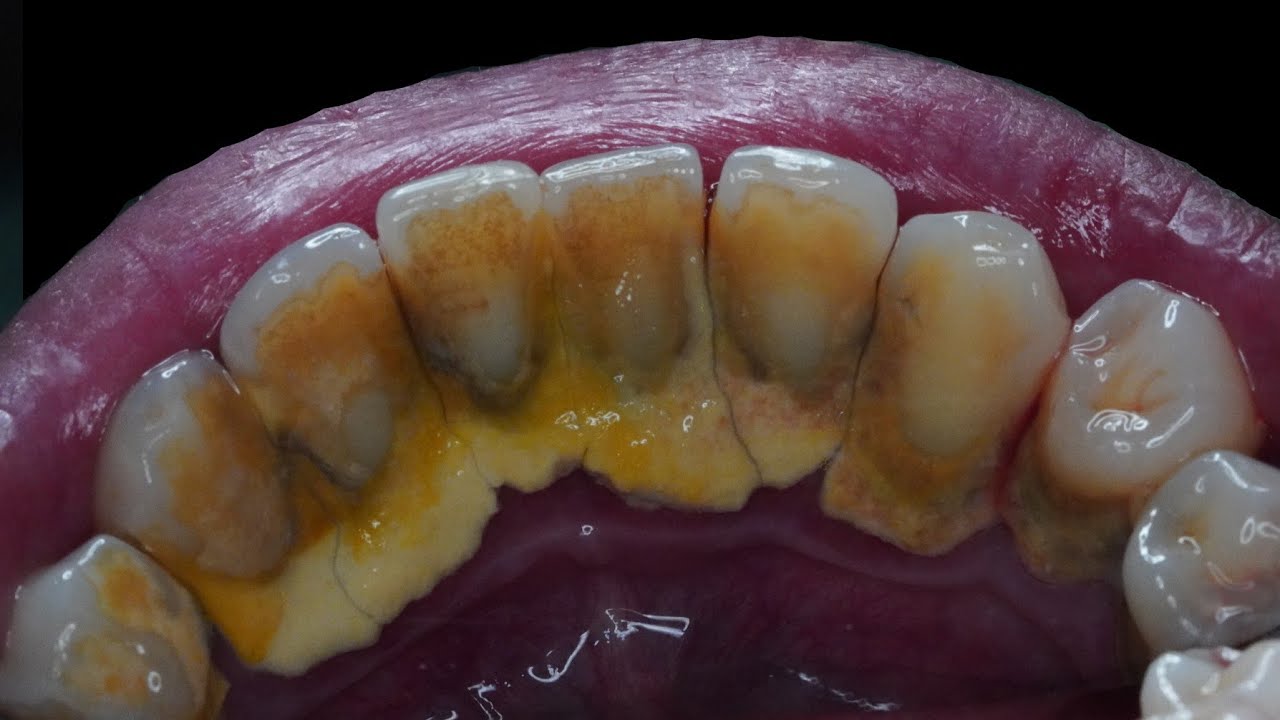

EXTREME CALCULUS REMOVAL (Male, 42yo) Dentist Dokter Gigi Tri Putra Dental Calculus Removal Youtube Understanding how to effectively remove calculus, or tartar, from your teeth is crucial for maintaining good oral health. Watch the removal of 20 years of dental calculus and plaque. Most of us brush our teeth every day (or at least claim to) but. When plaque is not effectively removed through brushing and flossing, it can mix with minerals from saliva. Dental Calculus Removal Youtube.

HEAVY CALCULUS TARTAR REMOVAL Dentist Dokter Gigi Tri Putra YouTube Dental Calculus Removal Youtube The most extensive calculus removal we have ever performed at our office. When plaque is not effectively removed through brushing and flossing, it can mix with minerals from saliva and harden into tartar. Here’s a detailed guide on what calculus is, why it’s harmful, and how you can ensure its removal: One popular home remedy for treating calculus formations on. Dental Calculus Removal Youtube.

How To Remove Difficult & Tenacious Calculus (Tartar) YouTube Dental Calculus Removal Youtube The most extensive calculus removal we have ever performed at our office. Nemeth has seen countless patients with excessive #calculusbuildup or #tartar that needs to be removed. When plaque is not effectively removed through brushing and flossing, it can mix with minerals from saliva and harden into tartar. Oil pulling is a dental care technique in which an individual. Unreal. Dental Calculus Removal Youtube.

20 Years of Dental Calculus Removed with Ultrasonic and IV Sedation Dental Calculus Removal Youtube Nemeth has seen countless patients with excessive #calculusbuildup or #tartar that needs to be removed. Oil pulling is a dental care technique in which an individual. When plaque is not effectively removed through brushing and flossing, it can mix with minerals from saliva and harden into tartar. The most extensive calculus removal we have ever performed at our office. Watch. Dental Calculus Removal Youtube.